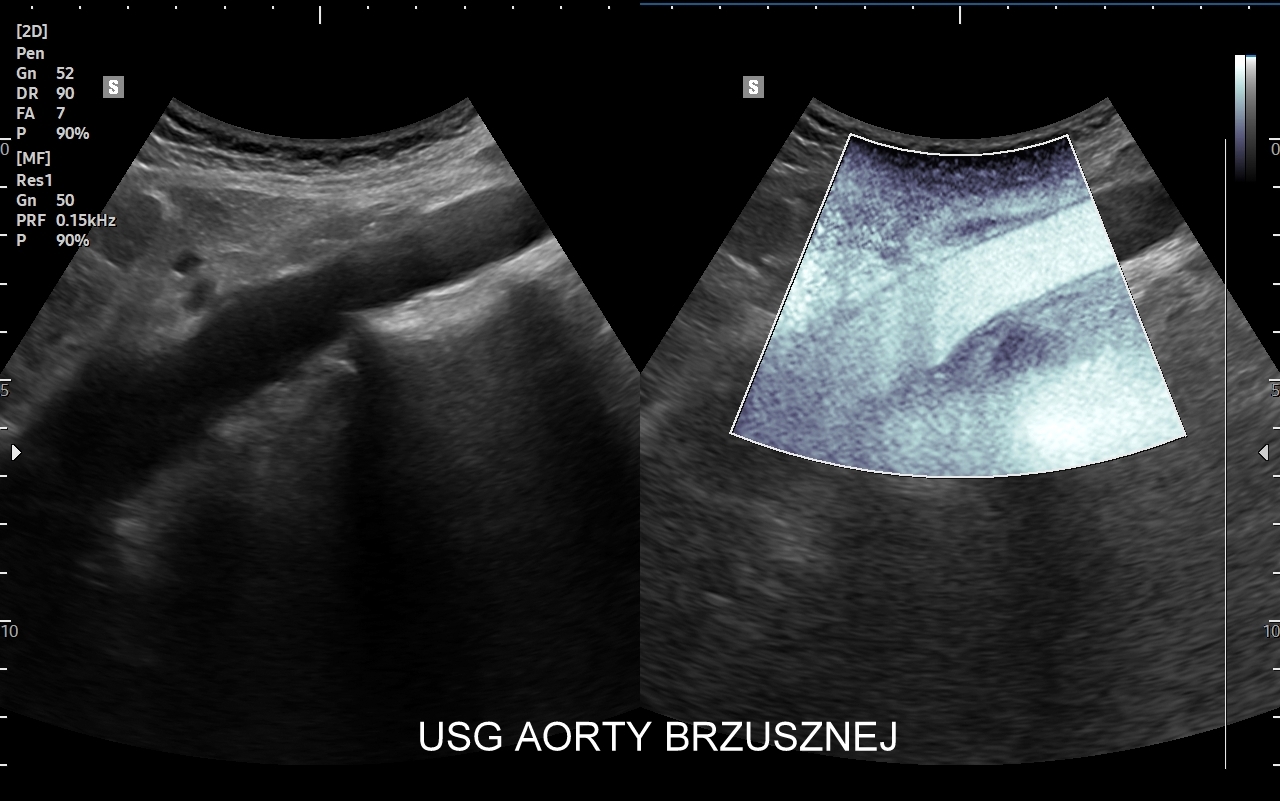

USG aorty i tętnic biodrowych

Badanie USG Doppler aorty brzusznej i tętnic biodrowych jest częścią standardowego USG jamy brzusznej. Nierzadko wykonywane jest jednakże jako badanie celowane w przypadku oceny tętniaków aorty brzusznej i tętniaków tętnic biodrowych, rozwarstwień aorty, zwężeń miażdżycowych występujących na podziale aorty lub w obrębie właściwych tętnic biodrowych. Funkcjonalne badanie aorty i tętnic biodrowych przeprowadza się także w ramach diagnostyki zaburzeń wzwodu i bólów zlokalizowanych w pośladkach. W pracowni dr Szczepańskiego zbadać można również w USG aortę piersiową w zakresie aorty wstępującej, łuku aorty i aorty zstępującej. Otóż należy mieć na uwadze, iż w obrębie aorty piersiowej lokalizować mogą się takie schorzenia jak tętniaki, rozwarstwienia, koarktacja aorty, czy choroby zapalne.

Badanie USG Doppler aorty, USG tętnic biodrowych, tętnic trzewnych (pień trzewny, tętnica śledzionowa, tętnica wątrobowa, tętnice krezkowe) wymaga przygotowania tożsamego jak do USG brzucha, tzn. na wizytę optymalnie należy zgłosić się rano oraz całkowicie na czczo, tj. bez rannego spożywania posiłków ani napojów. Na ok. 2 dni przed badaniem USG Doppler w obszarze brzucha zaleca się unikanie przejadania się, spożywania pokarmów wysokokalorycznych oraz słodyczy; nie wolno również spożywać kawy ani tzw. napojów energetycznych. Przyjmowanie Espumisanu nie jest obowiązkowe.